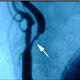

Providence Vascular Program is one of the leading multidisciplinary vascular programs on the West Coast that includes collaboration among interventional radiology, interventional cardiology, vascular surgery, neurosurgery, neurology, and vascular medicine specialists working together to care for our vascular clients. More »